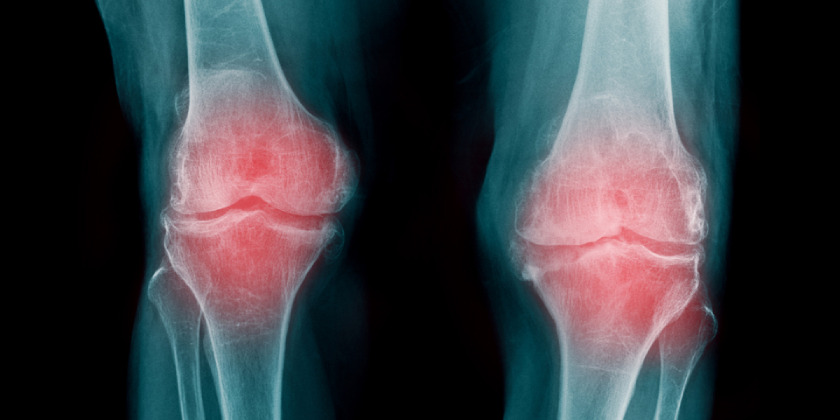

- Artrosis de rodilla

Este tipo de artrosis se caracteriza por el deterioro que genera el cartílago, provocando que se genere dolor con la actividad física, problemas para caminar y permanecer de pie. Esta enfermedad aparece en las personas antes de los 50 años de edad.